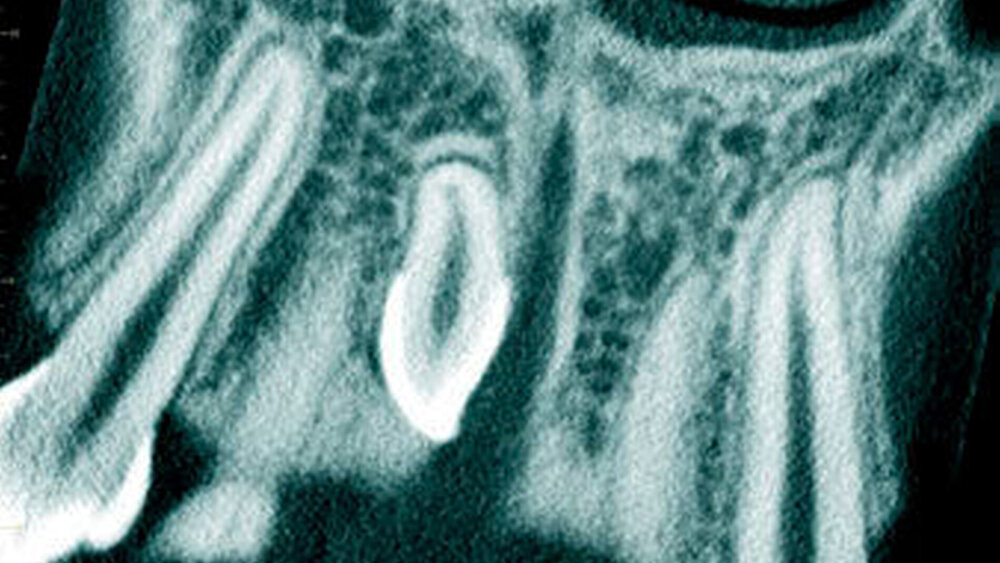

In einer aktuellen Arbeit berichteten Mossaz und Mitarbeiter (2014) über eine relativ hohe Prävalenz (22,8 Prozent) der Wurzel- resorptionen an benachbarten Zähnen, wobei besonders häufig überzählige Prämolaren zu Resorptionen führen (Abbildung 18). Für die Beurteilung der Wurzelresorptionen wurden digitale Volumentomografie (DVT) der Patienten herangezogen. In einer Studie aus China, welche ebenfalls DVT-Bilder beurteilte, wurde über eine deutlich geringere Häufigkeit von Wurzelresorptionen (1,6 Prozent) berichtet [Liu et al., 2007]. Im Gegensatz zu den Daten aus der Schweiz war Diagnose und Bewertung von Wurzelresorptionen kein primäres Ziel dieser Studie und es wurde auch keine Information über das Ausmaß der Resorptionen gegeben.

Daher könnte diese Studie leichte oder mäßige Wurzelresorptionen nicht eingeschlossen haben, was zumindest einen Teil des doch deutlichen Unterschieds in den Prozentsätzen erklären würde. Studien, welche Panoramaschichtaufnahmen zur Diagnose von Wurzelresorptionen heranziehen, berichten über Resorptionsraten zwischen 4,7 Prozent [Gündüz et al., 2008] und 7,6 Prozent [Hyun et al., 2009]. Tyrologou und Mitarbeiter (2005) berichteten sogar, dass keine Resorption im untersuchten Patientengut vorhanden waren. Allerdings wurden in dieser Studien nur Mesiodentes beurteilt, wo Wurzelresorption benachbarter Zähne eher selten vorkommen [Mossaz et al., 2014]. Generell lässt sich festhalten, dass zweidimensionale Röntgenaufnahmen für die Diagnose von Wurzelresorptionen eher ungenau sind und diese so in bis zu 50 Prozent der Fälle übersehen werden [Ericson Kurol, 1987, Heimisdottir et al., 2005; Botticelli et al., 2011; Alqerban et al., 2011a].

Überzählige Zähne können lange Zeit asymptomatisch bleiben und werden daher nicht selten erst zufällig diagnostiziert. Es werden aber auch eine Vielzahl an möglichen klinischen Komplikationen wie Zahndurchbruchstörungen, Lageverschiebungen/Rotationen sowie Wurzelresorptionen an benachbarten Zähnen und auch Zystenbildung in der Literatur beschrieben. Eine Wurzelresorption an Nachbarzähnen wird in bis zu 22,8 Prozent der Fälle im entsprechenden Röntgenbild beobachtet, wobei besonders häufig überzählige Prämolaren zu Resorptionen führen.

• Überzählige Zähne können zu diversen klinischen Komplikationen wie Zahndurchbruchstörungen, Lageverschiebungen/Rotationen sowie Wurzelresorptionen an benachbarten bleibenden Zähnen und auch zu einer Zystenbildung führen. Wurzel- resorptionen an Nachbarzähnen werden in bis zu 22,8 Prozent der Fälle im entsprechenden Röntgenbild diagnostiziert, wobei dies besonders häufig bei überzählige Prämolaren beobachtet wurde.